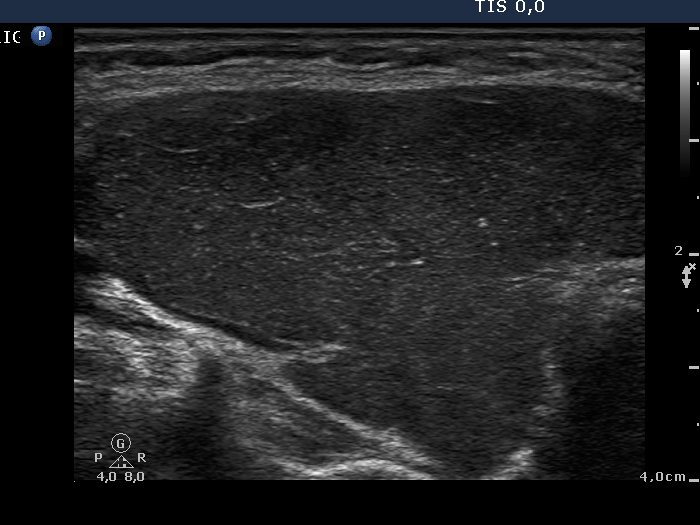

Ultrasonography: A hypoechogenic, inhomogeneous thyroid was found with increased vascularization.